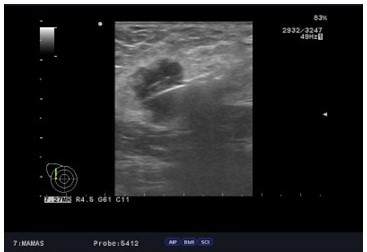

Presentamos el caso de una paciente 53 años, quien consulta refiriendo aumento de volumen en región axilar izquierda de 1 año de evolución. Al examen físico sin evidencia a la palpación de lesiones mamarias, se aprecia en la axila izquierda plastrón ganglionar de 4 cm de diámetro movible, no fijo a estructuras vecinas. En los estudios realizados, como lo son mamografía, eco mamario y resonancia magnética de ambas mamas con gadolinio en marzo 2022, solo se observa, la presencia de lesión de ocupación de espacio en axila izquierda, sugestivo de plastrón ganglionar, sin lesiones subclínicas en las mamas (Figura1,2,3)

Al examen físico mamas grandes asimétricas, presencia de cicatrices de mamoplastia de aumento, portadora de implantes mamarios, no se palpan tumores mamarios, y en la axila izquierda plastrón ganglionar de 4 cm. de diámetro duro movible que no infiltra piel. En vista de los hallazgos clínicos y de imágenes se procedió a realizar biopsia ecoguiada con aguja gruesa de corte, el 11/ 04/ 2022, reportando la anatomía patológica biopsia ap 3542 22, carcinoma ductal invasor grado II, ausencia de componente de carcinoma in situ, desmoplasia acentuada, con resultados para inmunohistoquímica biopsia ap. 3542 22 RE, + RP + ERB 2 neu negativo KI 67: 10 % subtipo molecular intrínseco tipo luminal A (Figura 4).